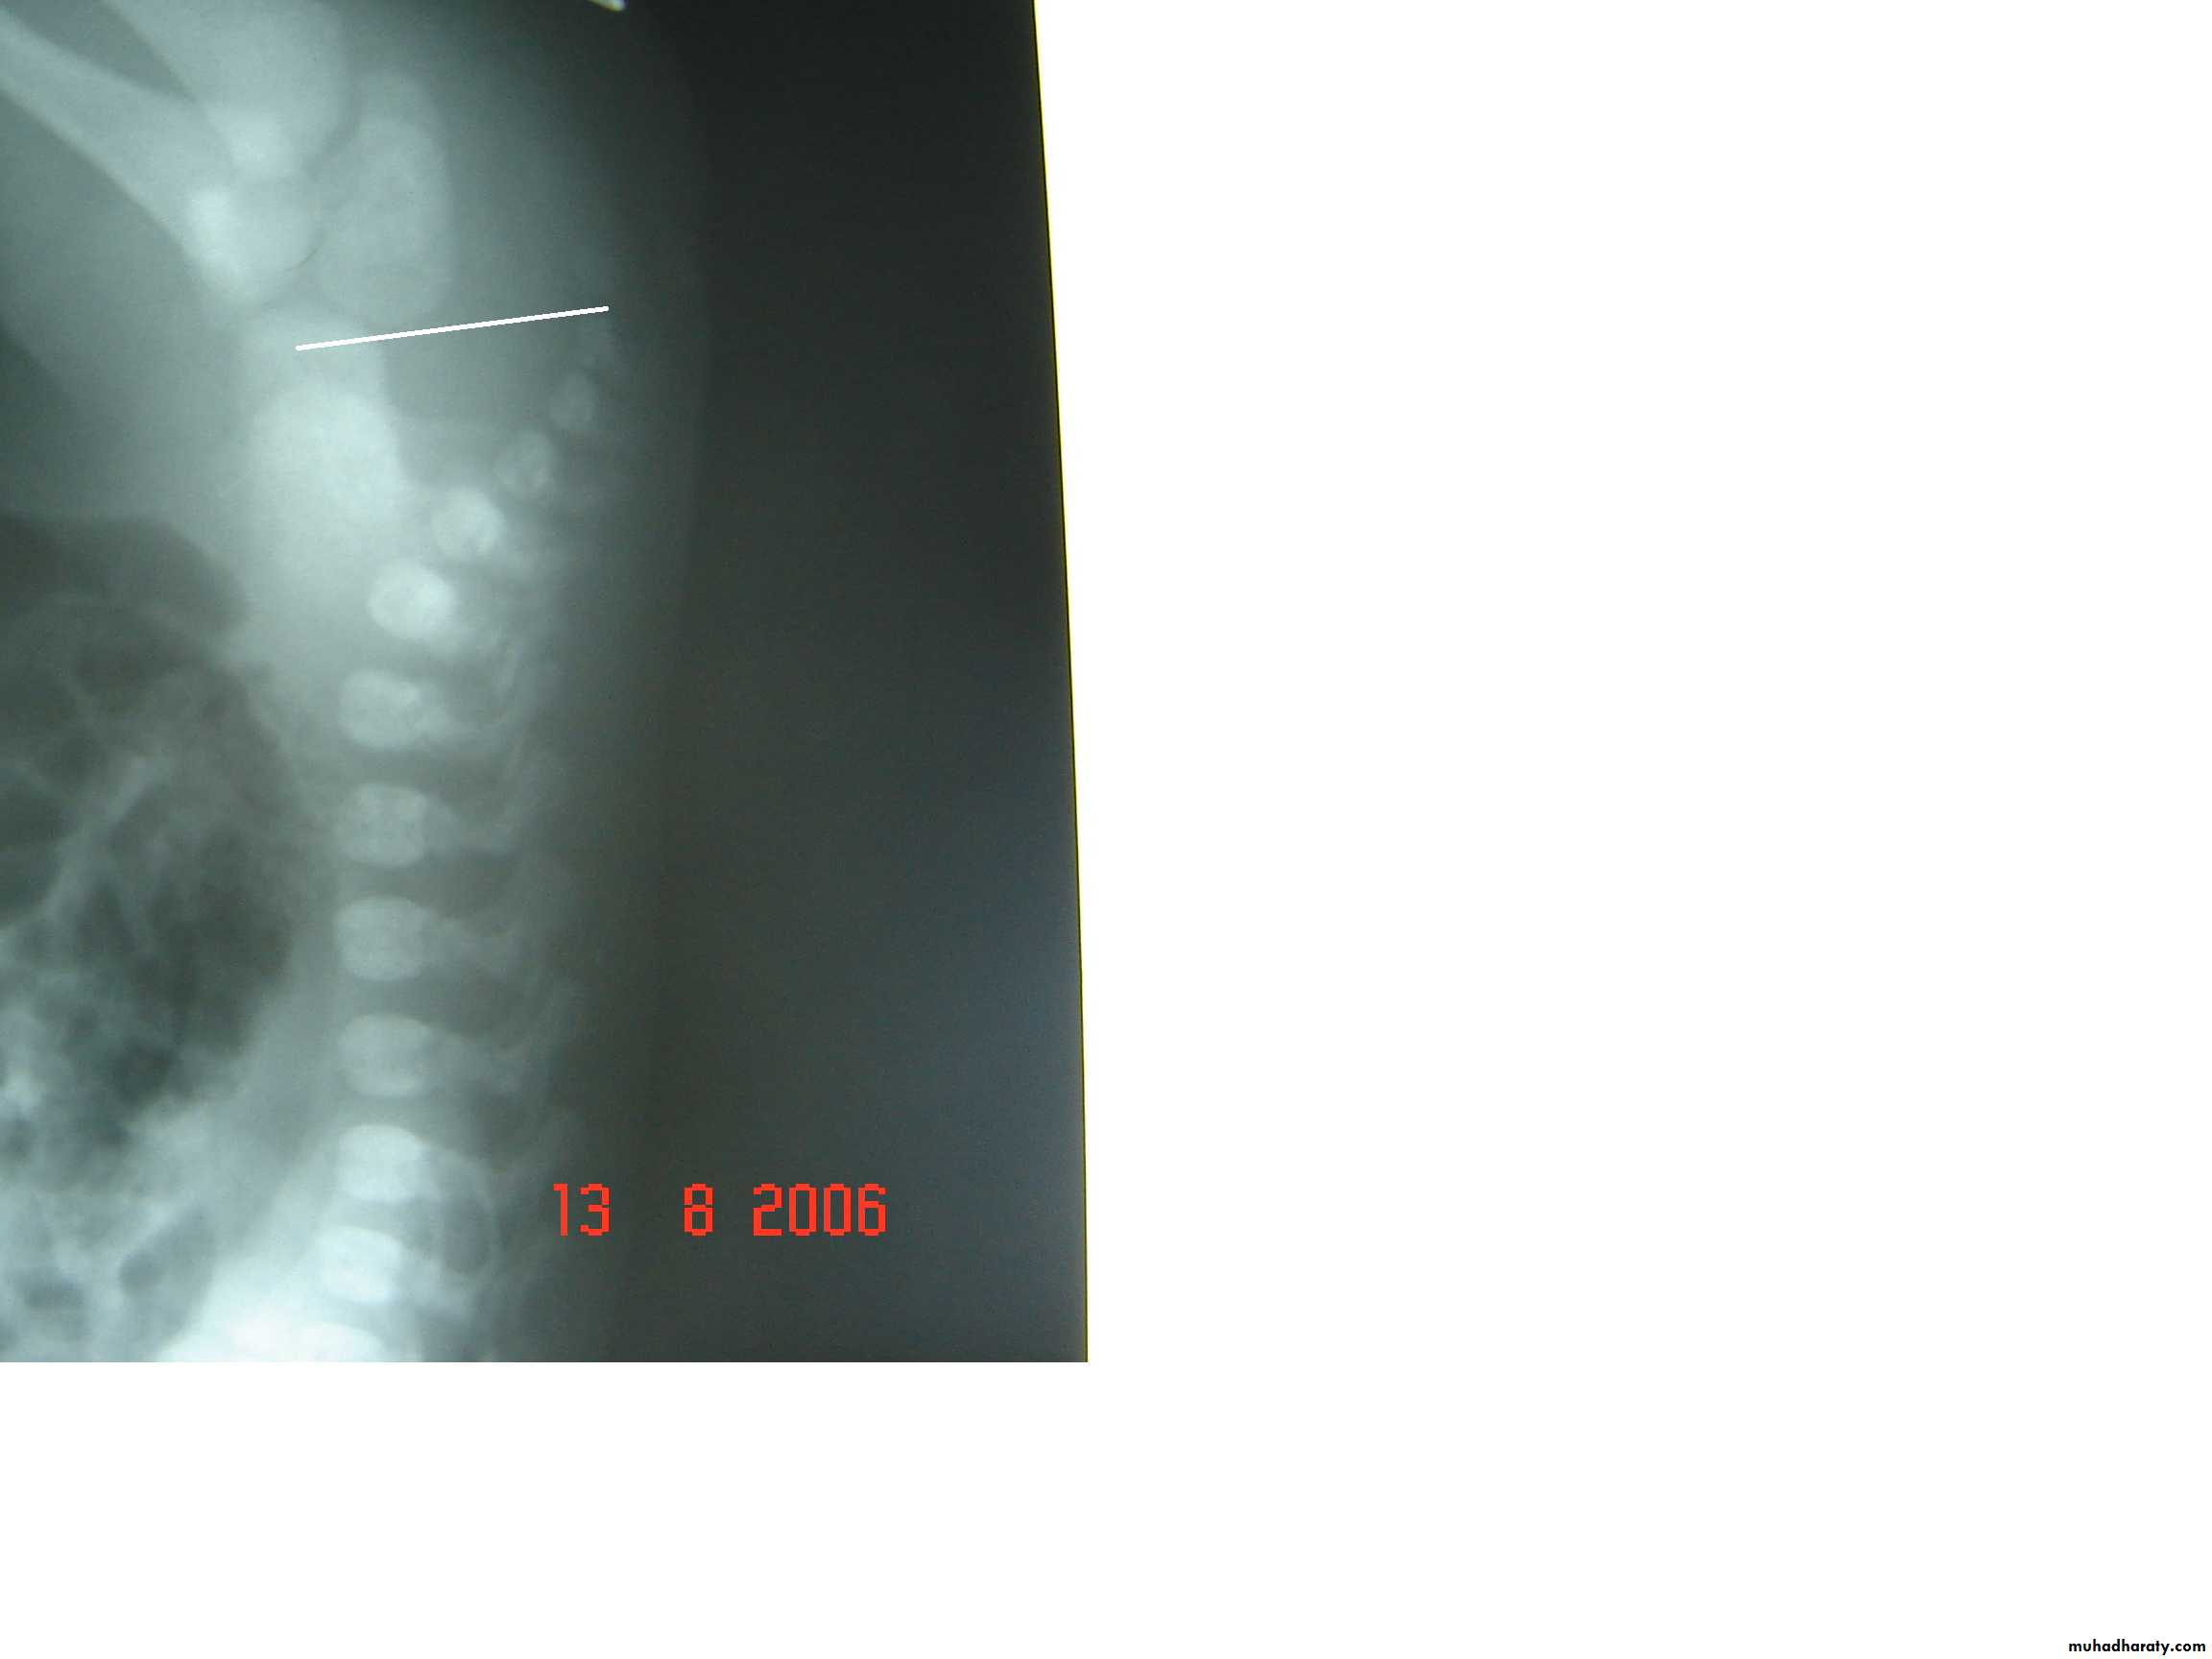

Radiology

Determined:

1-relation of rectum to sphincter muscle.

2-associated anomalies.

1-x-ray of the spine and chest (sacral , VATER).

2-Lateral invertogram ( pubococcegeal line) 18-24hr.after birth.

-gas shadow above this line suggest high type.

- gas shadow below suggest low type.

3-lateral decubitus X-ray.